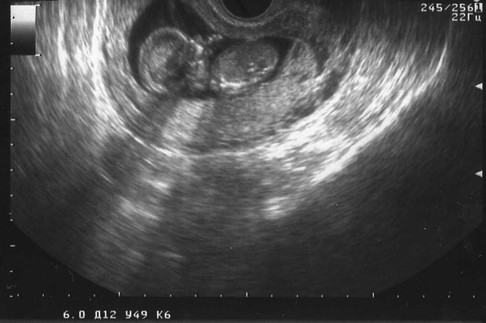

На двери отделения надпись: «Специализация — невынашивание беременности». Символично. Я приехала «на сохранение». Первое направление — на узи. Врач-узист, прервав переговоры с менеджером какого-то автосалона, пояснил: «На данном сроке мы ищем аномалии у плода, приводящие к угрозе выкидыша». Нашел:

— Один показатель высоковат, это по последним данным говорит о повышенном риске рождения ребенка с хромосомными аномалиями, такими, например, как…

— Да-да, я понимаю, спасибо, — пытаюсь выбежать поскорей. Хромосомные аномалии — это чаще всего синдром Дауна. Или Эдвардса. Что тут скажешь?

— Врач даст направление на генетическую экспертизу, — слышу в дверях как сквозь ватный матрас на голове.